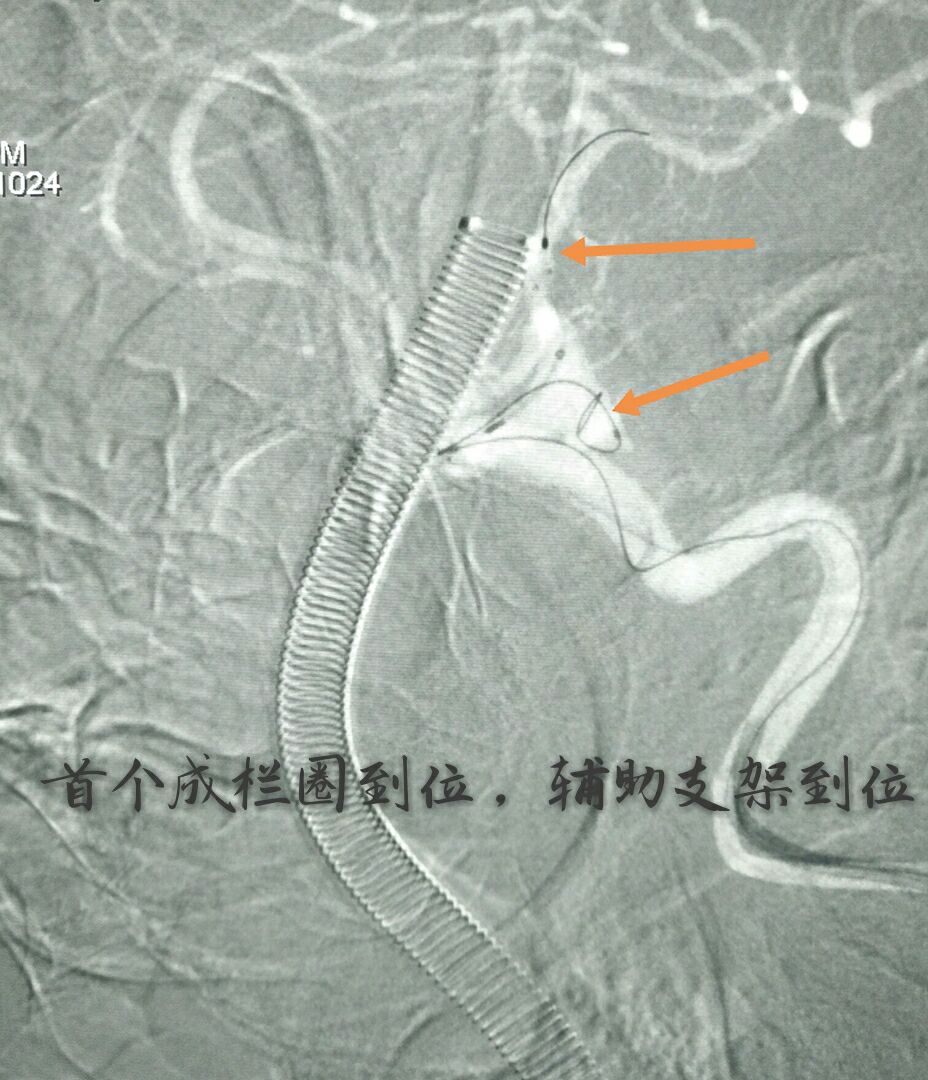

病例四:80岁男性患者,主症:头痛、脑鸣2年,DSA示左侧大脑中动脉下干大动脉瘤,绝对宽颈,载瘤动脉累及程度重

因栓塞难度大,术前做了详细、精准的计划

最准致密栓塞动脉瘤,载瘤动脉完美塑型并受到保护,难点:瘤颈极宽,辅助支架导管通过动脉瘤到达远端困难,最准微导管塑型成大弯,微导丝成袢通过动脉瘤到达远端,成功释放支架,动脉瘤栓塞后患者头痛、脑鸣症状消失